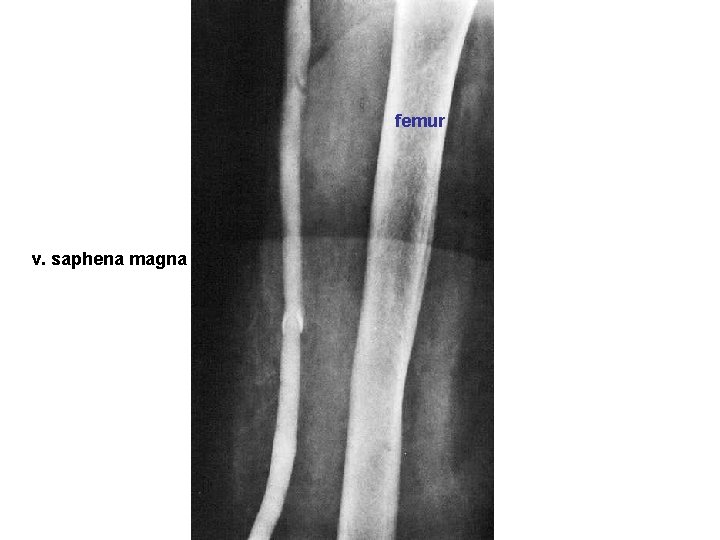

femur v. saphena magna

V. SAPHENA MAGNA - v. saphena accessoria - v. epigastrica spf. - v. circumflexa ilium spf. - vv. pudendae ext. vv. perforantes